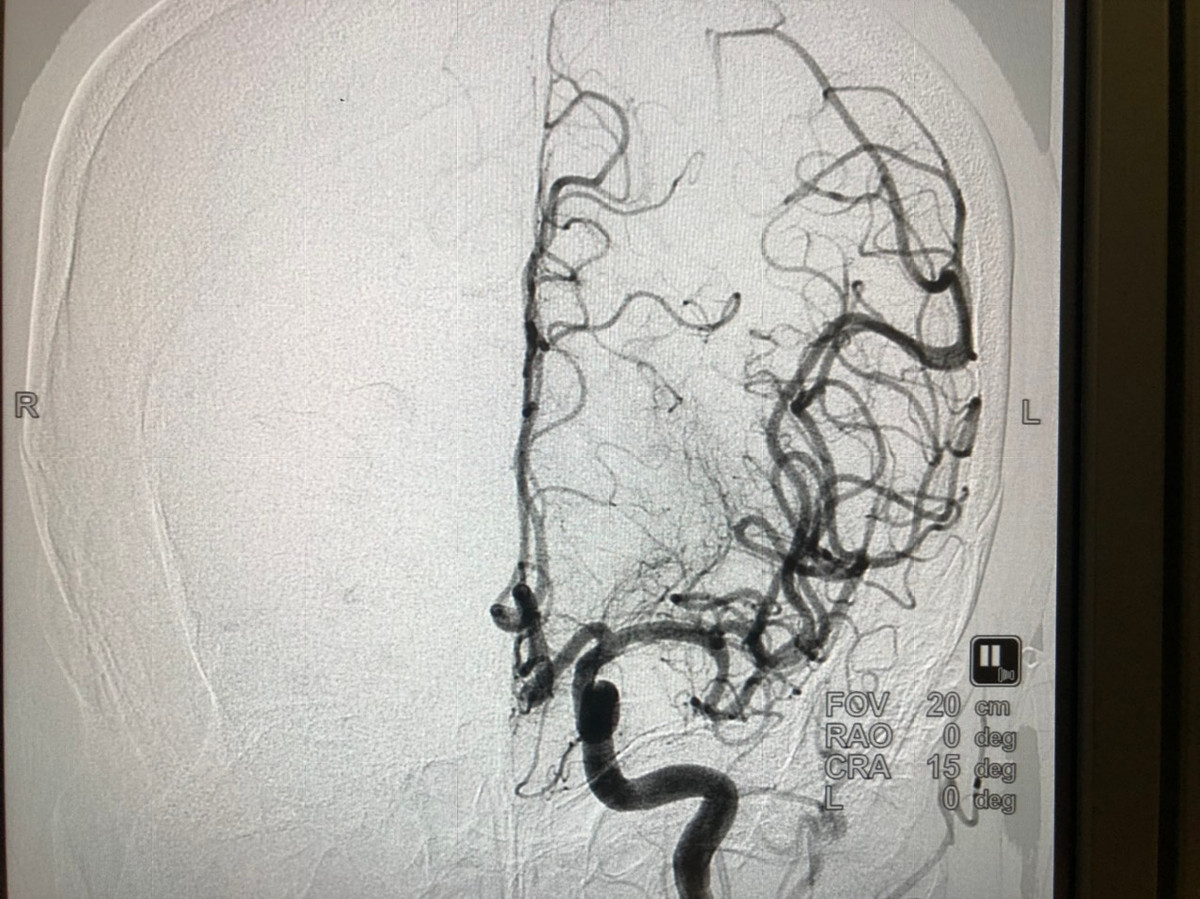

![]() |

| Hình sau khi lấy cục huyết khối ra và mạch máu đã đc tái thông. |